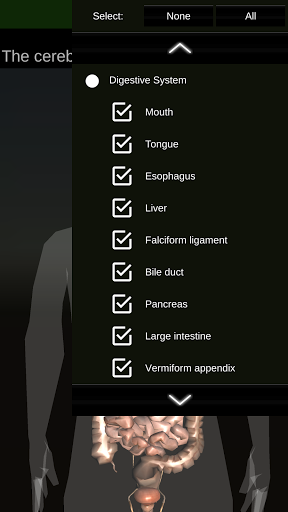

(الأجهزة الداخلية في)

Internal Organs 3D Anatomy 3.4

يمكنك هنا تنزيل ملف حزمة تطبيق أندرويد "Internal Organs 3D Anatomy" الخاصة بجهازVodafone Smart N9 Lite مجانًا، نسخة ملف حزمة تطبيق أندرويد - 3.4 للتحميل على Vodafone Smart N9 Lite اضغط ببساطة على هذا الزر. إنه سهل وآمن. نحن نقدم فقط ملفات حزمة تطبيق أندرويد الأصلية. إذا انتهكت أية مواد موجودة في الموقع حقوقك قم بإبلاغنا من خلال